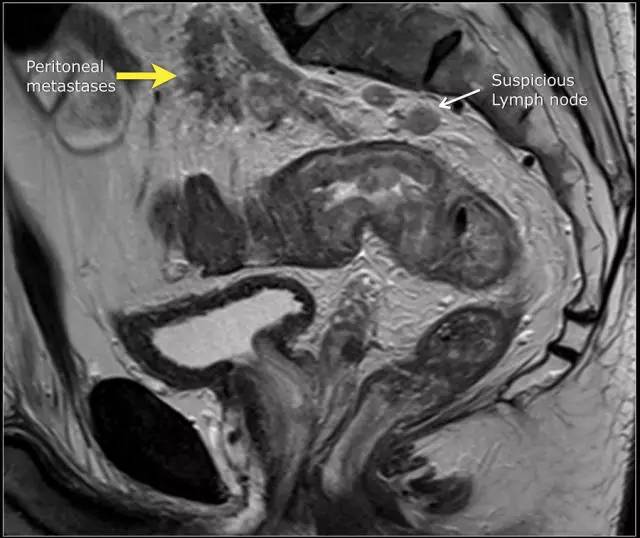

T4a 分期,侵出腹膜反折

低直肠完全被直肠内筋膜覆盖。在直肠中部,其后侧和外侧由直肠内筋膜覆盖,但在前侧由内脏腹膜覆盖。内脏腹膜生长意味着扩散到腹膜腔。在矢状 T2 加权图像上,腹膜反折可以描绘为连接膀胱与直肠前后方面的低信号细线。

图 14 轴向 T2 加权图像上,沿着内脏腹膜有肿瘤向内生长(箭头)

图 15 同一患者腹膜转移的矢状图(箭头),在直肠内还有可疑的淋巴结